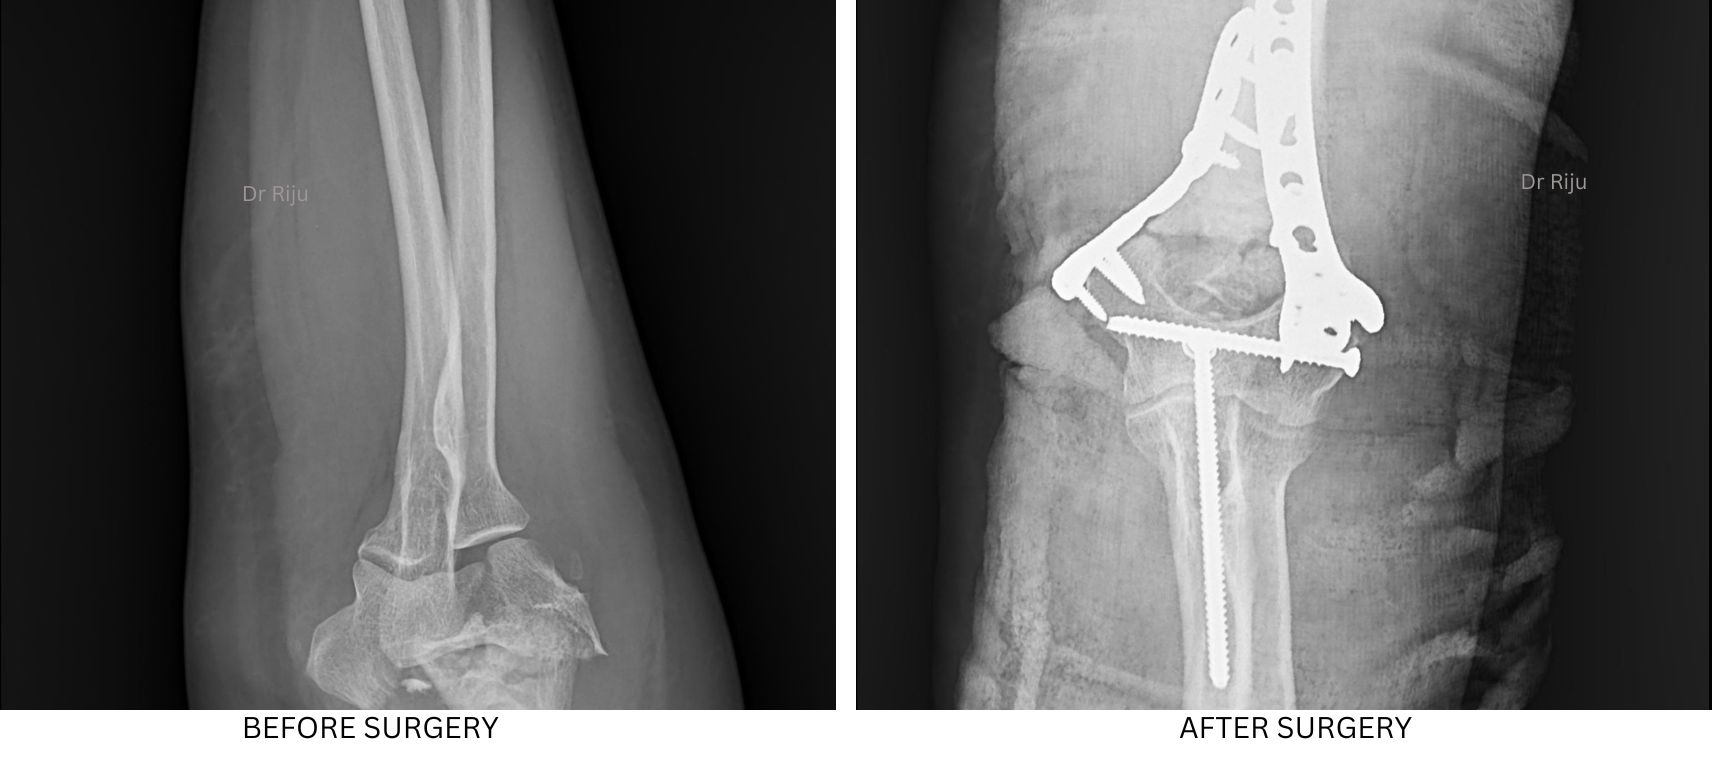

Image Gallery